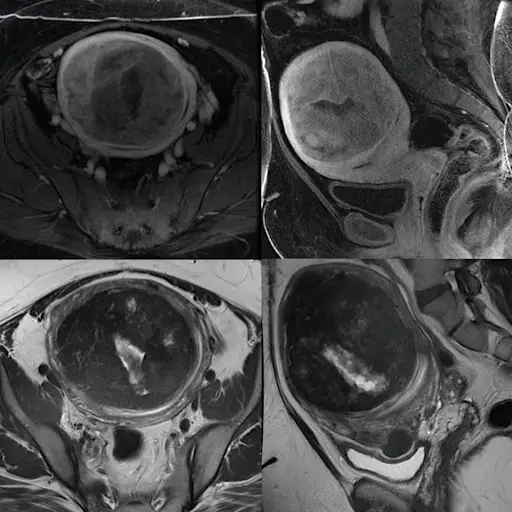

子宫肌瘤

iStock

肌瘤位置影响生育能力

当涉及肌瘤所在的生育能力时,最大的不同。“肌瘤就像房地产一样。它的位置,位置,位置。” Segars博士说。医生定义子宫肌瘤,也称为Myomas或Leioymyomas,基于它们在您体内的位置:粘膜粘膜肌瘤发生在子宫腔衬里;壁内肌瘤位于子宫壁;并在子宫壁外发现了亚肠肌瘤。(注意:您可以拥有一个以上的肌瘤,并且可以在一个以上的位置。)